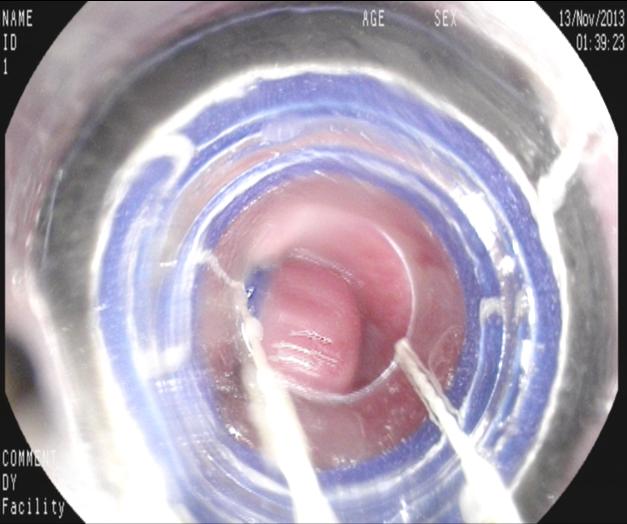

【九個(gè)月后復(fù)查】

九個(gè)月來(lái)患者無(wú)黑便及嘔血,復(fù)查胃鏡,食管內(nèi)曲張靜脈基本消失,胃底曲張靜脈亦減輕?;颊咴俅纬鲅L(fēng)險(xiǎn)而減低。如下圖:

上4圖隱構(gòu)可見(jiàn)套扎后癍痕,及右上方時(shí)鐘1點(diǎn)鐘位置略充盈的靜脈,無(wú)紅色征,不連續(xù)。